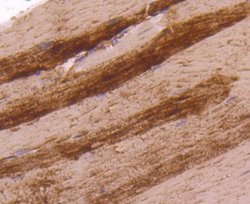

Lactate Dehydrogenase A/LDHA Monoclonal specifically detects Lactate Dehydrogenase A/LDHA in Human, Mouse, Rat, Zebrafish samples. It is validated for Western Blot, Flow Cytometry, Immunohistochemistry, Immunocytochemistry/Immunofluorescence, Immunoprecipitation, Immunohistochemistry-Paraffin.Specifications

| Western Blot 1:1000-1:5000, Flow Cytometry 1:50-1:100, Immunohistochemistry, Immunocytochemistry/Immunofluorescence 1:50-1:200, Immunoprecipitation, Immunohistochemistry-Paraffin 1:200-1:2000 | |